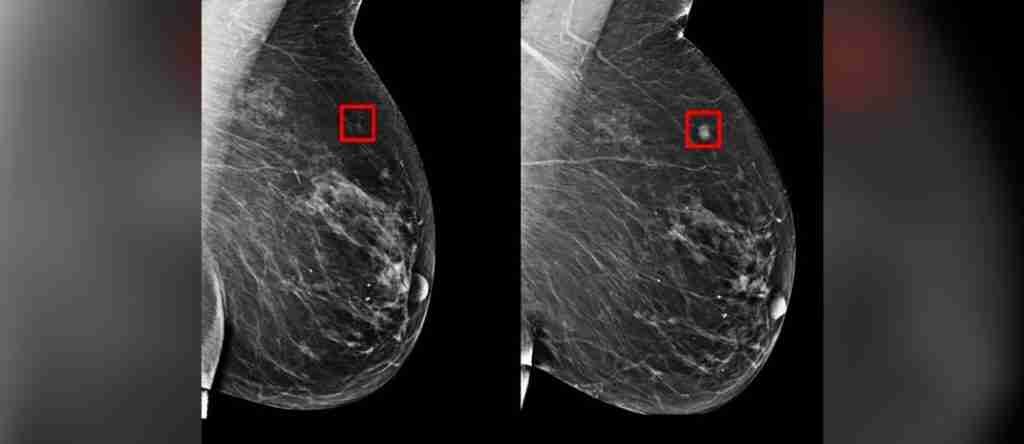

Un modelo basado en inteligencia artificial, ideado por un grupo de investigadores del Laboratorio de Ciencias de la Computación e Inteligencia Artificial y el Hospital General de Massachusetts, ha demostrado su capacidad para predecir la aparición del cáncer de mama con una anticipación de hasta cinco años.

Este sistema fue evaluado utilizando registros de mamografías entre los años 2009 y 2012, que cubren a más de 60 mil pacientes.

Este novedoso método de predicción del cáncer podría tener un impacto revolucionario en los tratamientos, ya que logra con precisión categorizar como pacientes de alto riesgo al 31% de todos los individuos con cáncer, en comparación con el 18% que es identificado por los modelos tradicionales.

A pesar de los continuos avances en genética, en muchas ocasiones el diagnóstico del cáncer de mama llega tarde, lo que conduce a tratamientos agresivos con resultados no siempre favorables. La detección temprana de pacientes en riesgo, habilitada por este nuevo modelo de aprendizaje profundo, se convierte en un elemento esencial para anticipar, a través de una mamografía, si un paciente desarrollará cáncer en el futuro.